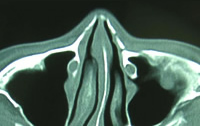

鼻骨の骨折は顔面骨の骨折の中で最も多い骨折です。受傷してから2~3週間以内であれば皮膚に傷つけずに治療することが可能です。原則的には、入院して全身麻酔による治療を行います。当科では、骨折の整復の状況(治り具合)を手術中に超音波診断装置を用いて評価することで、正確な治療を行っています。整復後は、鼻腔内にガーゼを詰めて、外側はプラスチック樹脂製のガードで固定を行います。受傷から1ヶ月以上経過した陳旧性では骨を切って整復する必要があります。その場合も鼻腔内の切開から行い表面には傷をつけずに行いますが、骨移植などを要することもあります。

| 鼻骨骨折CT像(整復前) | 鼻骨骨折CT像(整復後) |